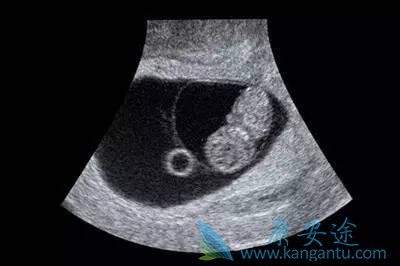

其实通过试管婴儿技术怀上宝宝和自然受孕,在孕期的检查项目相当类似,除了以下几次超声波检查。一起来看看吧! ...

一例成功的试管婴儿的过程主要有以下6个步骤: 1、促排卵治疗 由于不是每个卵子都能受精,不是每个受精卵都能发育成有活力的胚胎,因此要从女性体内获得多个卵子,才能保证有可以移植的胚胎,这就需要对女性进行促排卵治疗。 2、取卵 医生在B超引导下应用特殊 ...